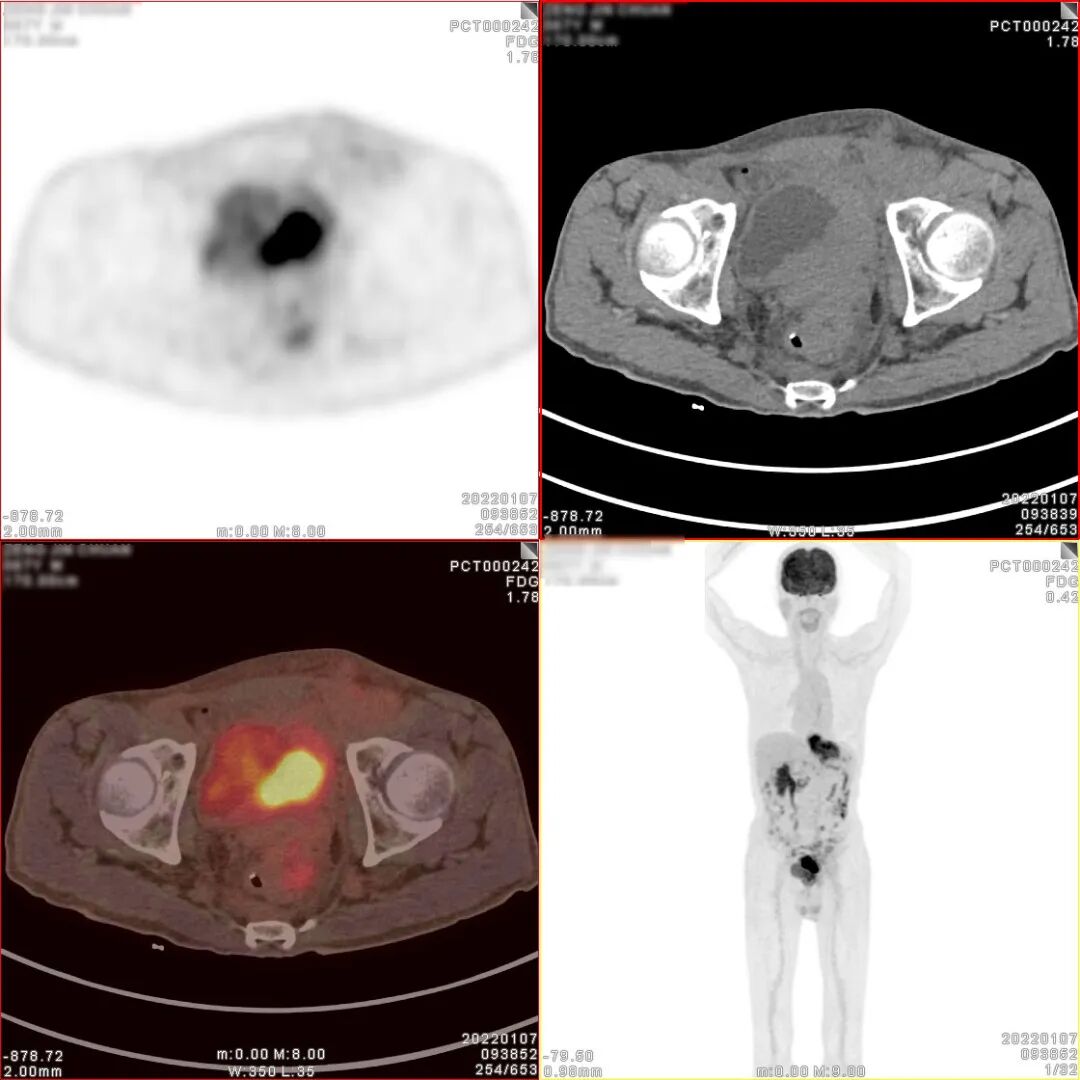

18F-FDG PET/CT检查图像

胃癌术后、化疗后,胃术后缺如,CT 见食管下段与肠道吻合口区软组织明显增 厚,密度较均匀,边缘欠清,PET 于相应部位可见不规则形放射性异常浓聚影,大小 约 71×27×63mm,SUVmax 为 9.5。CT 于左下腹部肠系膜上可见结节状密度增高影, 大小约 14×8mm,密度较均匀,边缘欠清,PET 于相应部位可见结节状放射性异常浓 聚影,SUVmax 为 4.9。CT 见腹盆腔其他部位肠系膜密度稍增高,边缘模糊,PET 于 相应部位未见明显放射性异常浓聚影。CT 见膀胱顶壁、左侧壁、左后壁及膀胱三角 区软组织明显增厚,密度较均匀,边缘欠清,堵塞双侧输尿管下段膀胱入口,并向 下与前列腺分界不清,PET 于增厚的膀胱壁内可见不规则形放射性异常浓聚影,大小约80×34×47mm,SUVmax 为 30.3;CT 见前列腺体积不大,其内可见多个小斑点状 高密度钙化影,PET 于前列腺内可见块状放射性异常浓聚影,大小约 39×36×35mm, SUVmax 为 6.9。CT 于盆腔内右侧髂外血管旁可见稍肿大淋巴结,大小约 10×7mm, PET 于相应部位可见结节状放射性异常浓聚影,SUVmax 为 2.9。

PET/CT诊断:

1、胃癌术后、化疗后,食管下段与肠道吻合口区软组织明显增厚,代谢增高, 考虑肿瘤复发病灶;

2、膀胱顶壁、左侧壁、左后壁及膀胱三角区不规则形代谢增高影及前列腺内块 状代谢增高影,考虑膀胱癌并侵犯前列腺;

3、左下腹部肠系膜上结节状密度增高影,代谢增高,考虑转移灶;腹盆腔其他 部位肠系膜密度稍增高,未见代谢增高,请结合临床追踪复查以排外低代谢腹膜 转移灶的可能;

4、盆腔内右侧髂外血管旁稍肿大淋巴结,代谢稍增高,不排外淋巴结转移灶的可能。